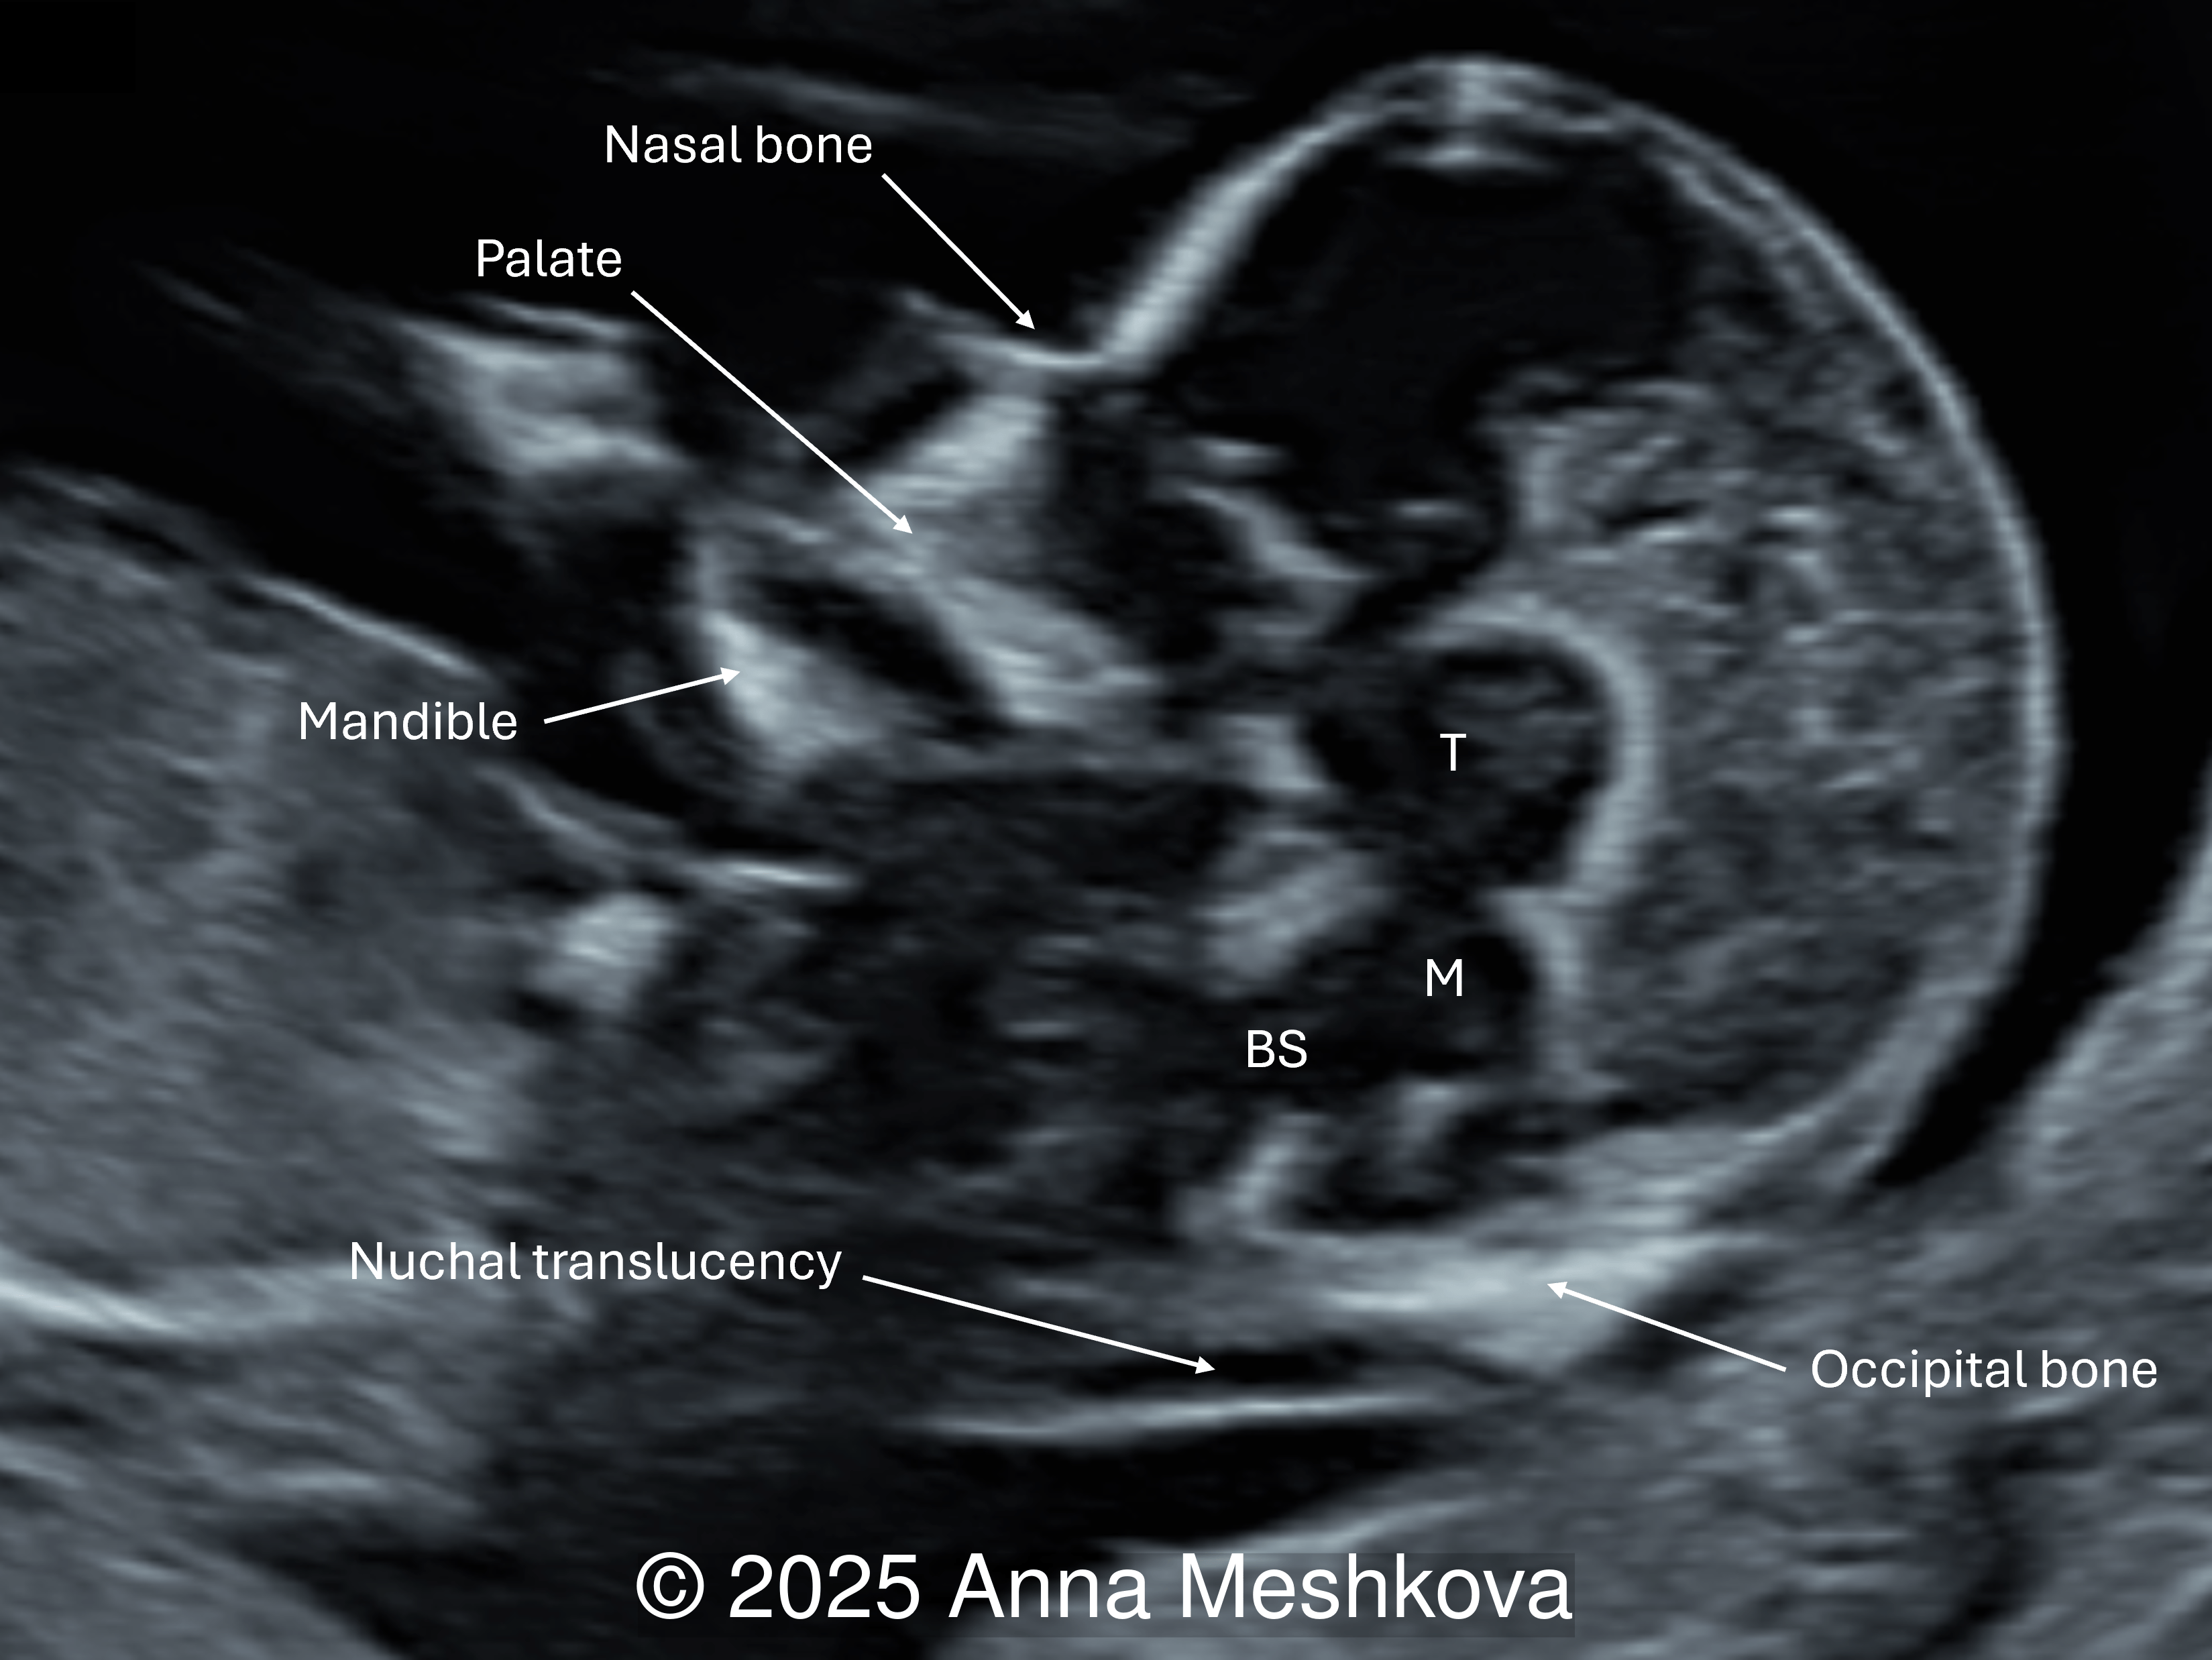

1. Intracranial translucency (IT) represents the fourth ventricle, which appears as a hypoechoic space in the mid-sagittal view of the fetal face. In open spina bifida, intracranial translucency may be absent or compressed due to Arnold-Chiari II malformation [1].

Normal fetus with intracranial translucency (IT) appearing as a fluid-filled space between the brainstem (BS) anteriorly and the choroid plexus of the 4th ventricle posteriorly. The future cisterna magna is present. (T: thalamus; M: midbrain)

Image 3 Normal fetus with intracranial translucency (IT) appearing as a fluid-filled space between the brainstem (BS) anteriorly and the choroid plexus of the 4th ventricle posteriorly. The future cisterna magna is present. (T: thalamus; M: midbrain)

In a fetus with spina bifida, some fluid remains visible, however the normal landmarks of the IT are absent. The choroid plexus and future cisterna magna are not clearly seen.

Image 4 In a fetus with spina bifida, some fluid remains visible, however the normal landmarks of the IT are absent. The choroid plexus and future cisterna magna are not clearly seen.